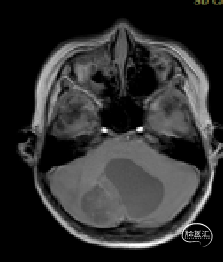

术前MRI

现病史:患者18个月前无明显诱因出现间断头痛,休息后可缓解,开始未予重视,未行特殊治疗。1周前患者无明显诱因出现恶心、呕吐,就诊于当地医院,行颅脑MRI提示:小脑囊实性占位性病变,首先考虑毛细胞星型细胞瘤。现患者为求进一步治疗就诊于我院,门诊以“脑肿瘤”收入院。患者自发病以来神志清,精神可,饮食睡眠正常,二便如常,体重未见明显下降。

小脑肿瘤(毛细胞型星形细胞瘤?)